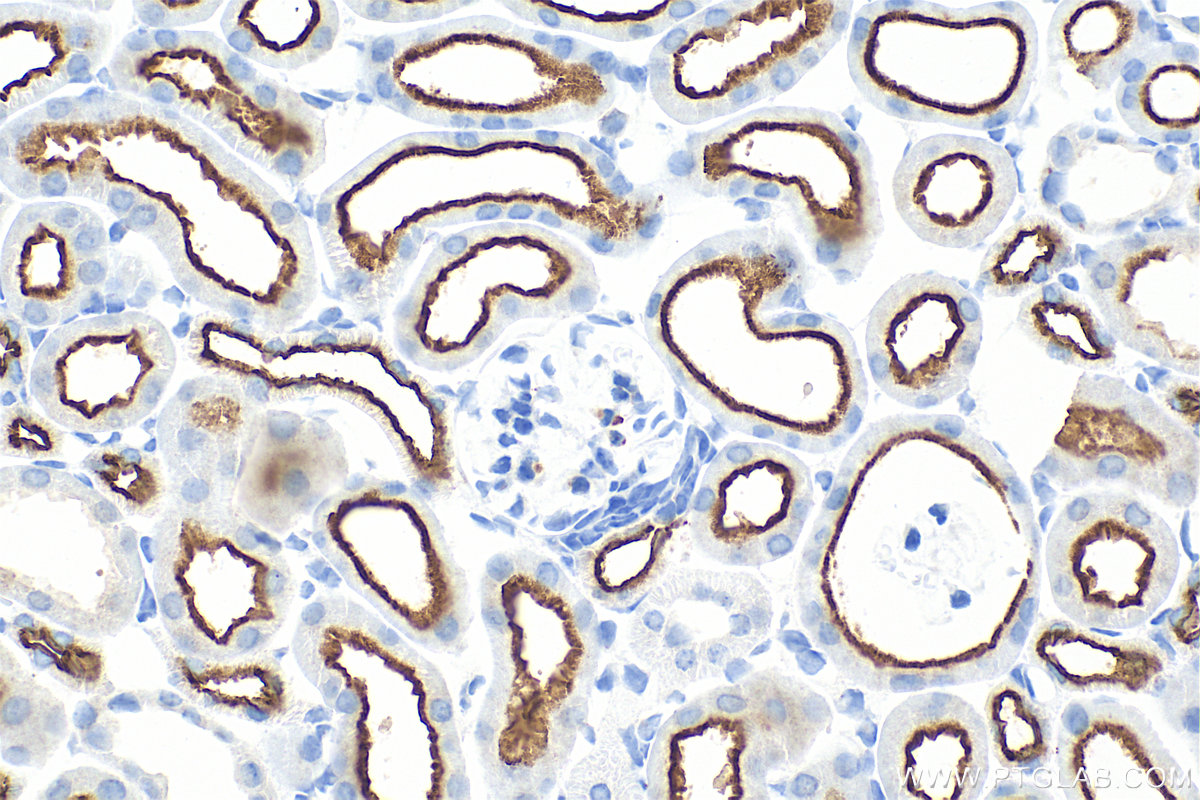

| Positive IHC detected in | mouse kidney tissue Note: suggested antigen retrieval with TE buffer pH 9.0; (*) Alternatively, antigen retrieval may be performed with citrate buffer pH 6.0 |

33559-1-AP targets SLC9A3/NHE3 in WB, IHC, IF-P, ELISA applications and shows reactivity with human, mouse samples.

SLC9A3, also known as NHE3, belongs to the sodium hydrogen exchange protein family (NHE) and is mainly responsible for regulating the concentration of sodium and hydrogen ions inside and outside the cell. SLC9A3 is a Major apical Na+/H+ exchanger in kidney and intestine, playing an important role in renal and intestine Na+ absorption and blood pressure regulation (PMID:24622516, 2635877). Mutations in SLC9A3 cause Congenital Sodium Diarrhea (PMID: 26358773, 31276831).